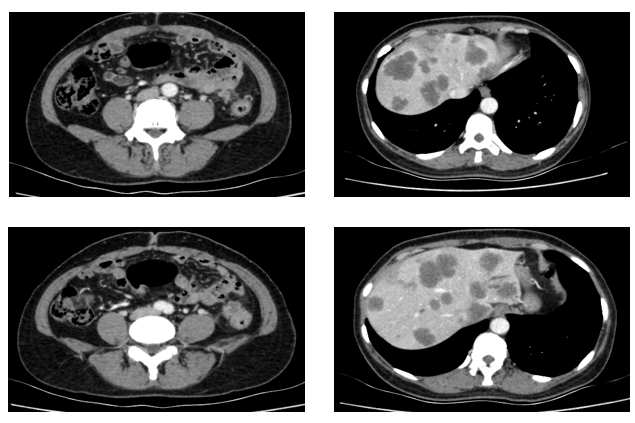

三线治疗(2022-9-7至2023-03-18,PFS:6月余):

2022-09-07至2023-01-03院外使用DS-8201治疗5周期。2周期后疗效评价:PR。CT示:腹膜后淋巴结较前部分缩小;双肺多发转移灶较前缩小。

残余病灶的手术切除:2023-02-22至外院行“左半肝切除术,尾状叶切除术,肝段切除术,胆囊切除术,腹腔淋巴结清扫术,肠粘连松解术,肾周围粘连分解术,肝脏肿物射频消融,肝动脉结扎,腔静脉损伤修复术”。

再次行基因检测,结果提示:HER2扩增倍数为5.49倍

CT(2023.4.14)提示:肾上腺病变较前增大,考虑PD